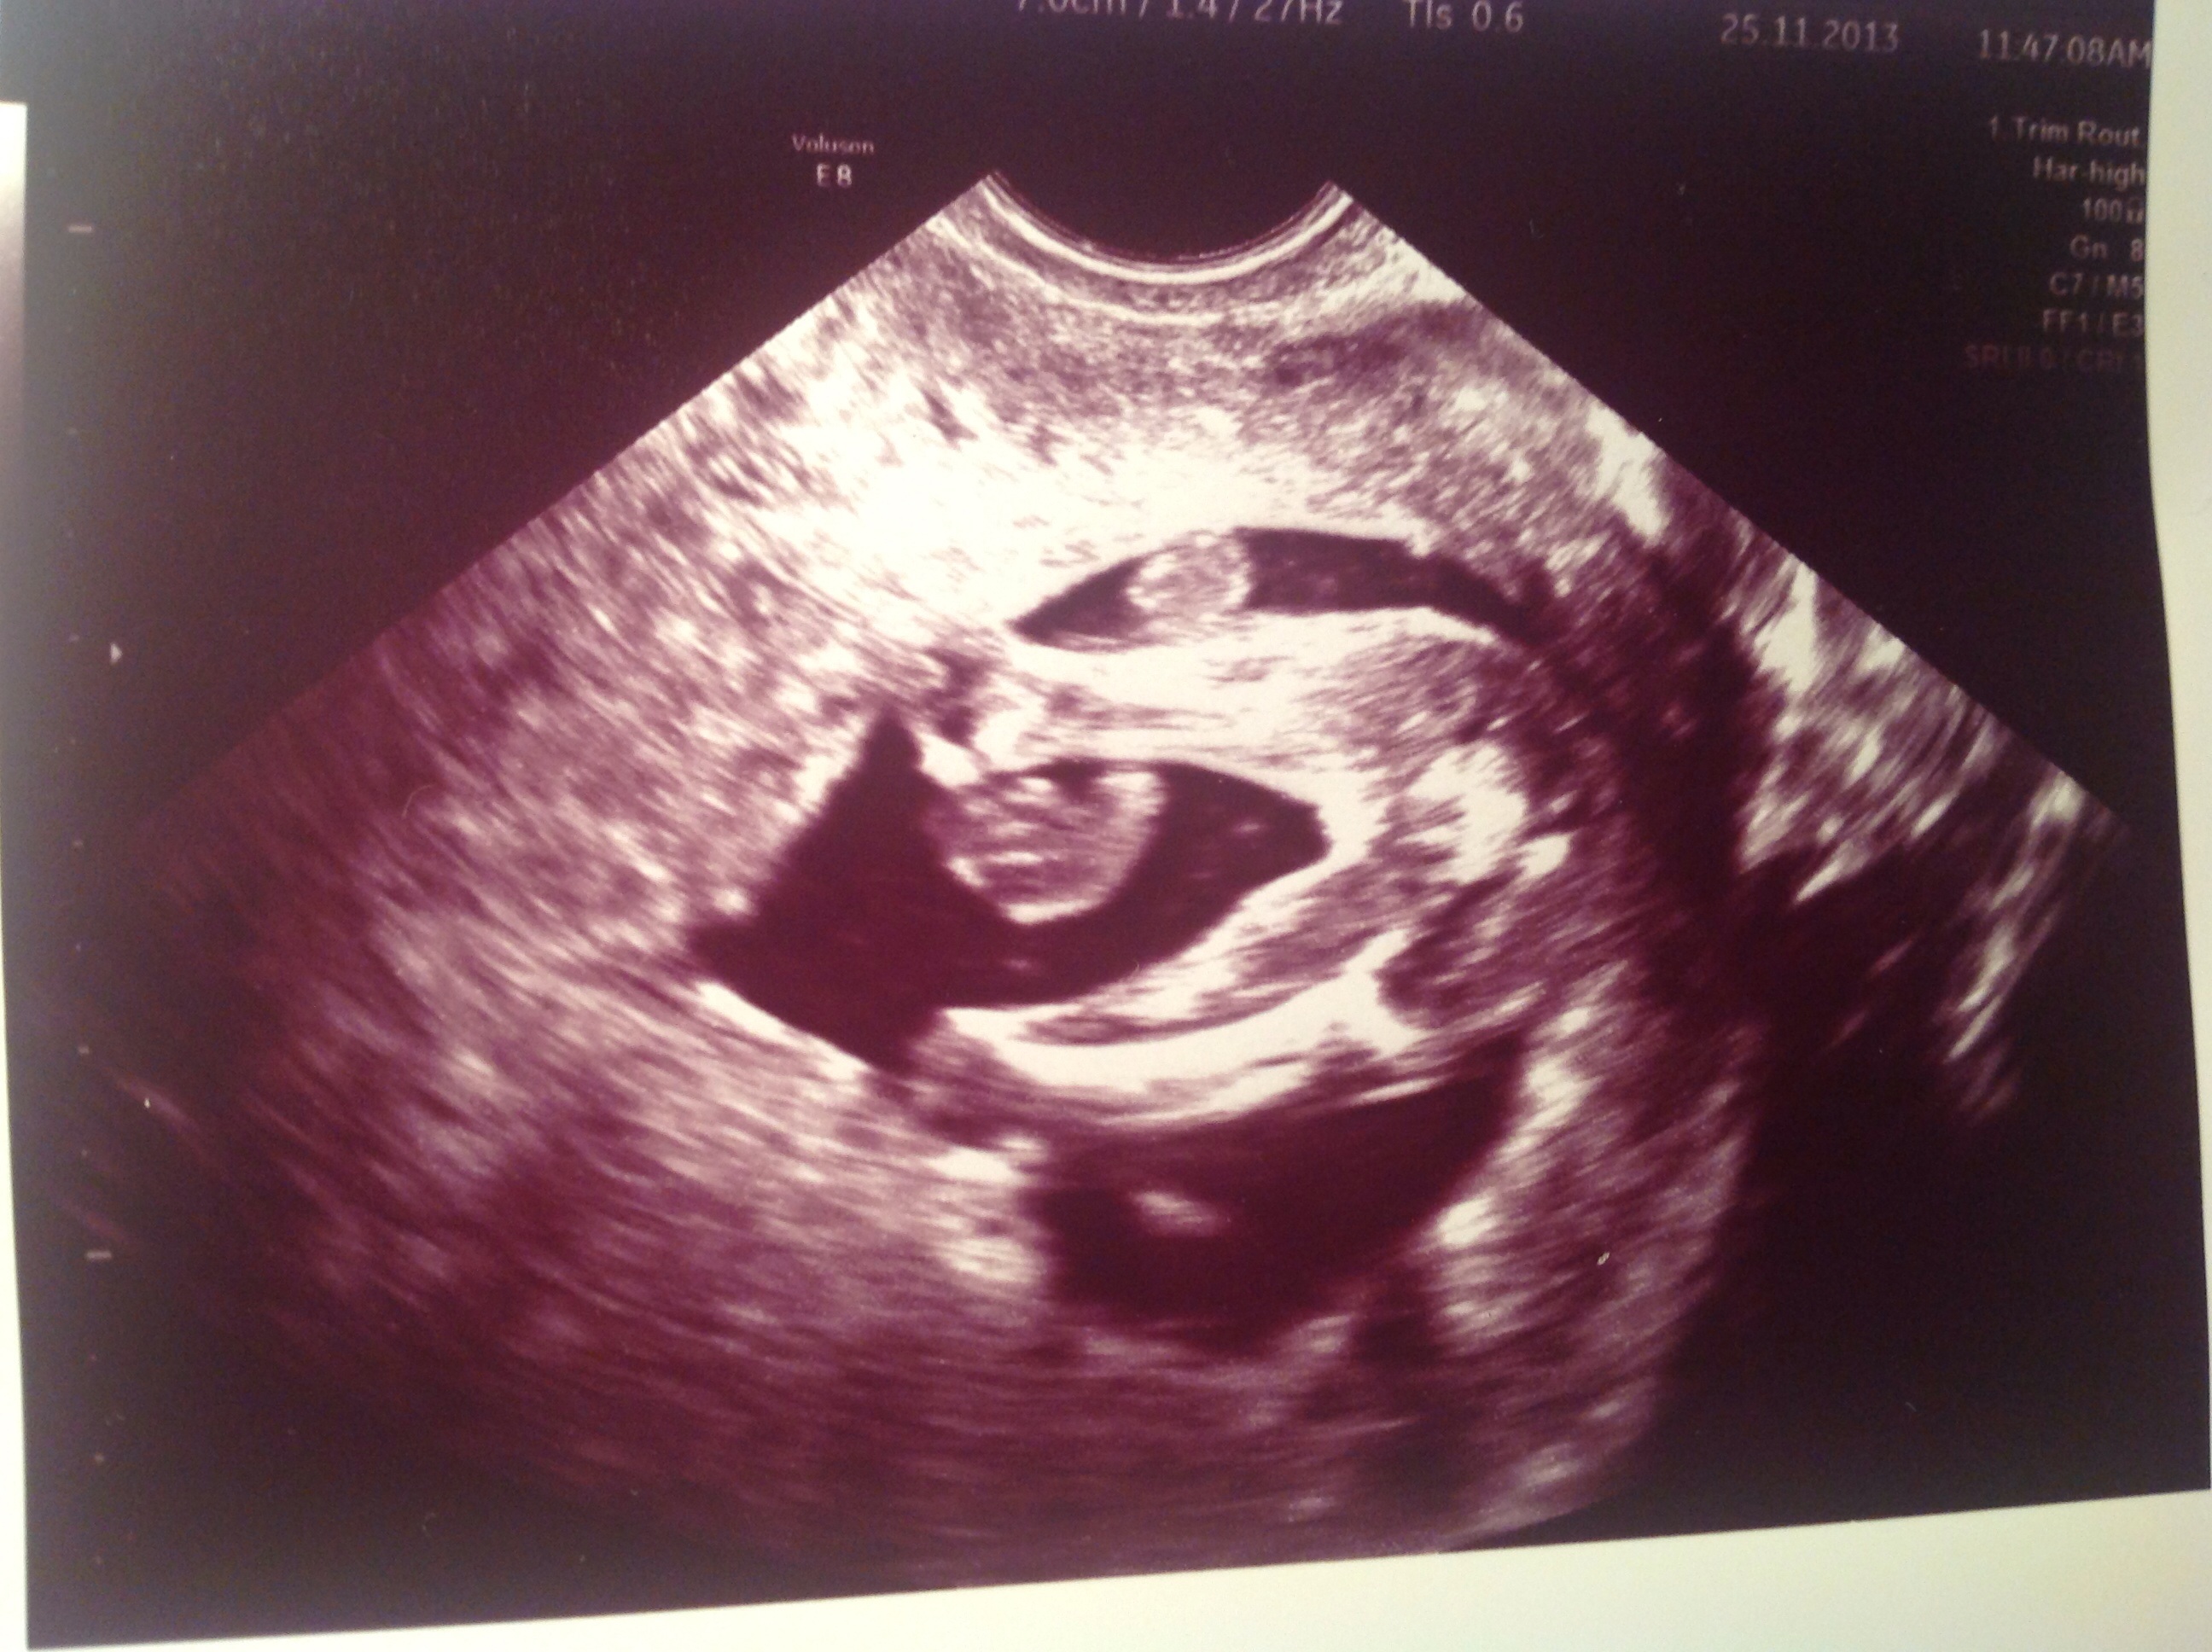

I had a private scan done today, 15+3. First she said I had to wait till 18 weeks, to be sure of gender.

She took a transvaginal scan, and she was very sure she only saw girl parts.

I really hope it is true. My routine scan is booked at week 19, 3 weeks from now at I really hope they can confirm!

Meanwhile, what do you think?